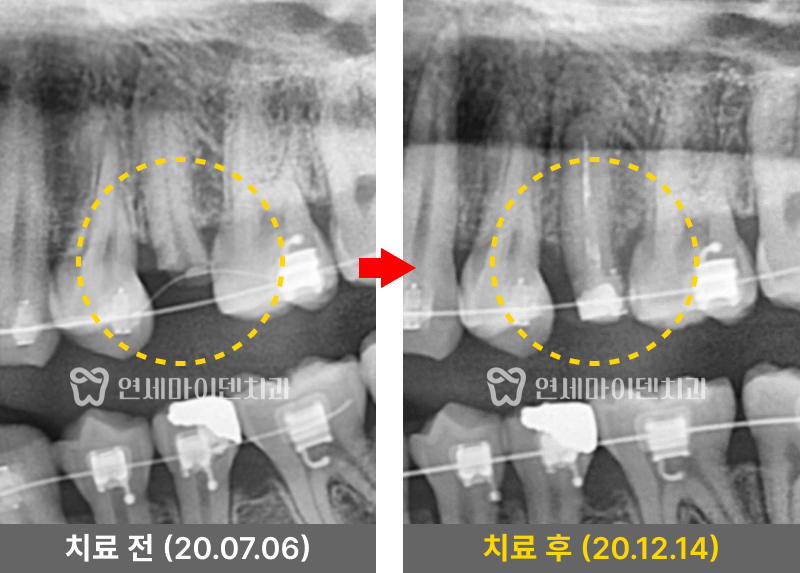

위쪽의 깨진 어금니 부위는

교정 기간 동안 임시치아를 부착하여 사용하였습니다.

정출이 완료된 후 크라운을 장착하여

심미적으로도 완성도 높은 결과를 얻을 수 있었습니다.

정출 과정에서는 잇몸 건강에 무리가 가지 않도록

생물학적 폭경인 3mm 이내에서만 진행했습니다.